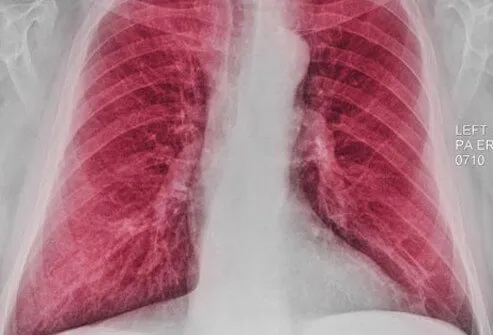

胸部X光

胸部 X 光檢查可能能夠顯示某些COPD患者可能出現(xiàn)的肺部增大(由于過(guò)度充氣)。但是,X射線(xiàn)更有用,有助于排除或排除可能導(dǎo)致類(lèi)似于COPD癥狀的其他問(wèn)題,例如肺炎。